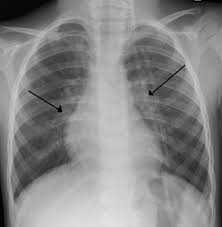

Non Small Cell Lung Cancer Nsclc Imaging Practice Essentials Radiography Computed Tomography from img.medscapestatic.com Lung cancer results in more fatalities in the united states than any other kind of cancer. Many people who are diagnosed with lung cancer say that their symptoms were first dismissed, even by doctors, as being due to a cold, bronchitis, or other infections. Lung cancer is the leading cause of cancer death in both men and women, and about 228,150 new cases will be diagnosed this year. Boop can mimic lung cancer.and lung cancer can quite easily be mistaken as a pneumonia. My mom's situation is a little different in that she had breast cancer over 11 years ago. Doctors can misdiagnose a serious case of pneumonia as: Pulmonary emboli are blood clots that have formed in other regions of the body and have then traveled to the lungs. It can also show the size, shape, and position of any lung tumors and can help find enlarged lymph nodes that might contain cancer that has spread.

Radiologic imaging is rarely diagnostic. In some cases, bronchitis can be chronic, meaning it lasts for more than a few months or keeps coming back. Boop can mimic lung cancer.and lung cancer can quite easily be mistaken as a pneumonia. Wheezing or hoarseness, which cause blockage or inflammation in the lungs. So far 2 biopsies have turned up negative for cancer, though the lesions are obviously suspicious for cancer.

It can also show the size, shape, and position of any lung tumors and can help find enlarged lymph nodes that might contain cancer that has spread. About 30% to 40% of people with lung cancer have some symptoms or signs of metastatic disease. Radiologic imaging is rarely diagnostic. Malignant tumors trigger inflammation in surrounding normal lung tissue, and they may obstruct your airways and interfere with normal airflow. In some cases, bronchitis can be chronic, meaning it lasts for more than a few months or keeps coming back. A recent scan for some clavicle swelling found 3 bone lesions and a lung nodule. Respiratory infections repeated infections such as pneumonia and bronchitis are common before lung cancer is diagnosed. Furthermore, lung cancer symptoms, such as a persistent cough, back pain or weight loss, can resemble a cold or bronchitis and may not raise suspicions of lung cancer. However, the symptoms of lung cancer differ vastly from bronchitis which is one of the commonest affections of chronic smokers. Wheezing or hoarseness, which cause blockage or inflammation in the lungs. However, it can occur in other heart and lung diseases. It can also be helpful to request a second opinion of any diagnosis if the recommended course of treatment does not promptly alleviate the issue. Costochondritis is most commonly associated with chest pain symptoms, and so are some types of cancer.